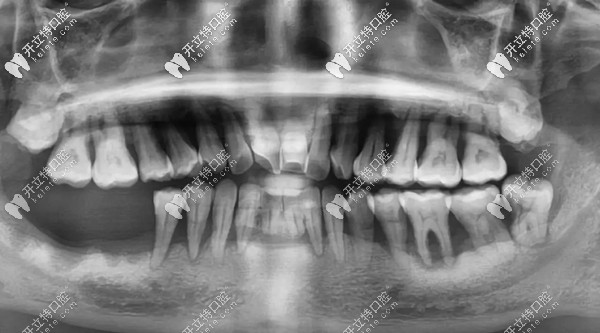

其實(shí)鄧?yán)蠋煹臐M口牙齒基本都在,但,一顆都留不住,因?yàn)槿慷紦u搖欲墜,牙根只有很淺一截在牙槽骨內(nèi),失去了咀嚼功能。

牙齒問題:①牙結(jié)石沉積 ;②重度牙周炎引起牙齦萎縮,牙根暴露;③牙齒楔形缺損;④四環(huán)素牙;⑤牙齒晚上痛到影響睡覺,痛的程度感覺已經(jīng)無法忍受了;⑥輕輕咬一點(diǎn)東西牙齒都在里面動(dòng)....

鄧?yán)蠋煹闹髟\醫(yī)生王鋒表示:“楔形缺損和四環(huán)素牙會(huì)使牙齒對外界刺激變得敏感,但讓全口牙齒松動(dòng),一吃東西就痛的“元兇”,其實(shí)是長年得不到治療的牙周病?!?/p>